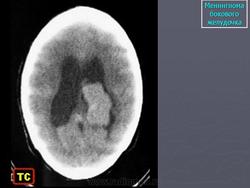

Менингиома

Приложения:

1.men_.slayd65.jpg2.men_.slayd66.jpg3.men_.slayd67.jpg4.men_.slayd68.jpg5.meng_.slayd69.jpg6.men_.slayd70.jpg7.men_.slayd71.jpg8.men_.slayd72.jpg9.men_.slayd73.jpg10.men_.slayd74.jpg11.men_.slayd75.jpg12.men_.slayd76.jpg13.men_.slayd77.jpg14.men_.slayd78.jpg15.men_.slayd79.jpg16.men_.slayd80.jpg17.men_.slayd81.jpg18.men_.slayd82.jpg19.men_.slayd83.jpg20.men_.slayd84.jpg